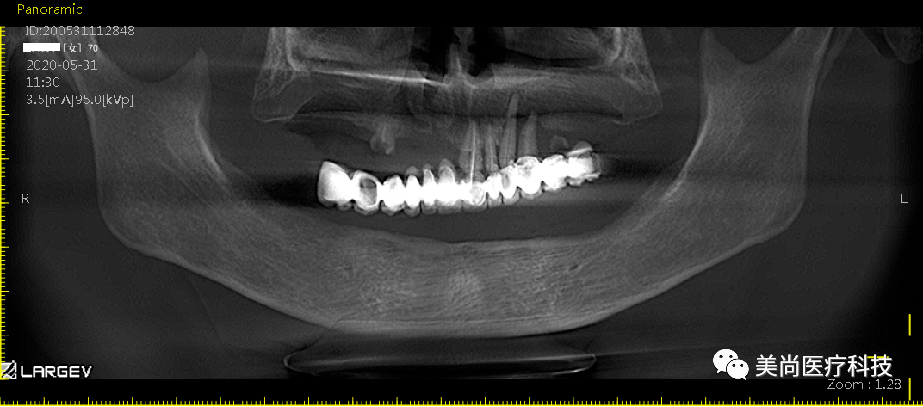

上颌可见烤瓷连桥修复Ⅲ°松动,牙龈微红肿;

下颌无牙颌附着龈狭窄仅1mm,牙槽嵴呈刀刃状;

32、42可用骨宽度6mm,可用骨高度10mm;

34、44可用骨宽度6mm,可用骨高度11.5mm。

牙列缺损;

21、22、23残冠;

14、25残根。